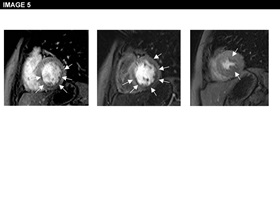

Physical examination is unremarkable. The resting ECG is normal with no ischaemic features (Image 1). She was referred for an ECG exercise stress test. She exercised for 6 min 35 seconds (Bruce protocol), achieved 131% of her heart rate and developed chest pain and breathlessness at peak exercise. Ischemic ST changes were noted which resolved slowly during recovery (Image 2). The patient was referred for cardiac catheterization which showed smooth unobstructed coronary arteries (Image 3). Provocation testing with acetylcholine was performed during angiography when incremental doses of acetylcholine 2mcg, 40mcg, 100mcg were injected in the left coronary system. This resulted in the reproduction of her symptoms, ST depression on the ECG and >75% diffuse epicardial coronary artery spasm of the left coronary artery (Image 4). The diameter of the coronary arteries returned to baseline after intracoronary nitrate administration and both the chest pain and the ECG changes subsided rapidly. Given the diffuse involvement of the distal segments of the coronary artery during the acetylcholine infusion, suggesting the presence of microvascular dysfunction, the patient underwent cardiac magnetic resonance perfusion scanning. Following adenosine stress, which reproduced her usual symptoms, the patient developed subendocardial hypoperfusion of the basal-mid inferior wall & adjacent septum & lateral wall with a circumferential pattern suggestive of microvascular angina (Image 5). On late gadolinium enhancement imaging there was no fibrosis or infarct (Image 6).